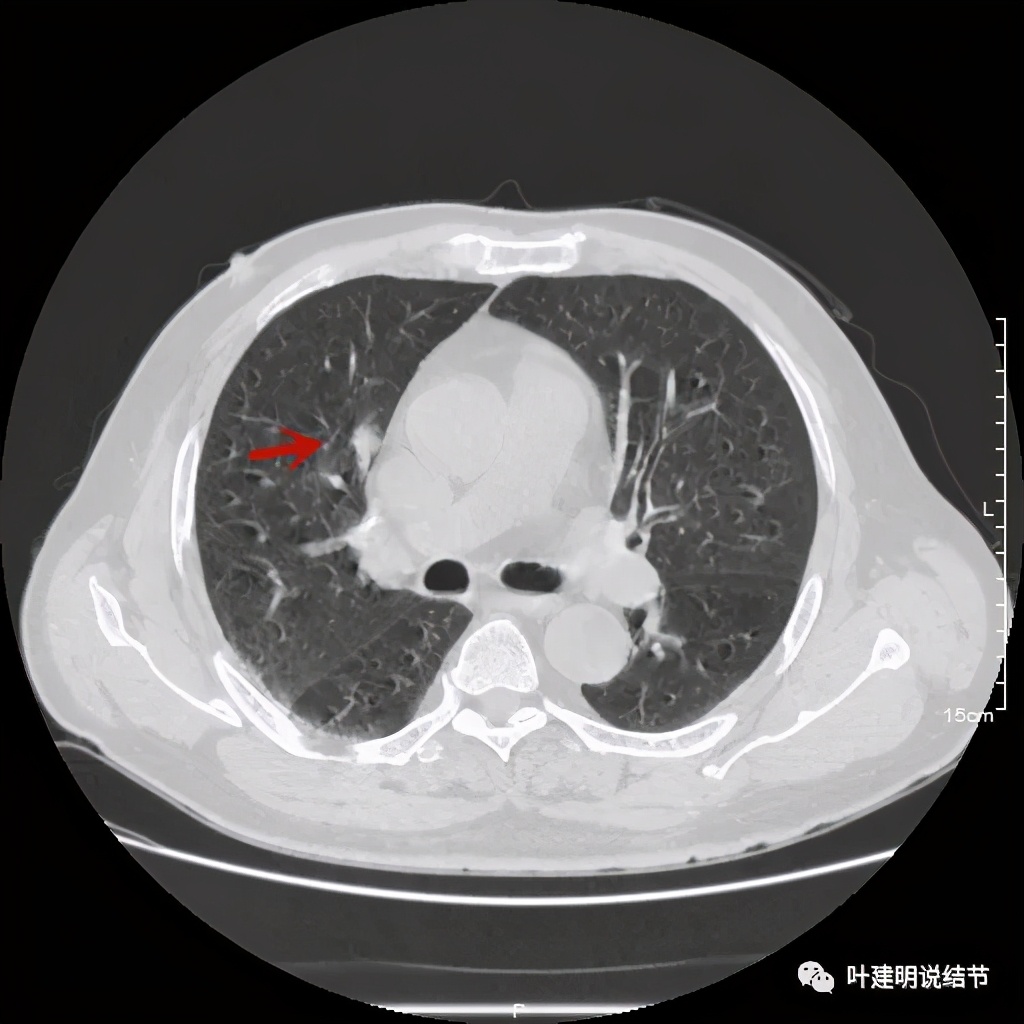

上图示病灶局部点状高密度(蓝色);边缘过于光滑(绿色)

上图示病灶密度不均,但边缘过于光滑(绿色);支气管似有截断(粉色);局部有点状钙化(蓝色)

上图也示病灶密度不均,但边缘过于光滑(绿色);支气管似有截断(粉色);局部有点状钙化(蓝色)

病灶在上图层面似见支气管也是贴壁的。那么增强后又是如何呢?